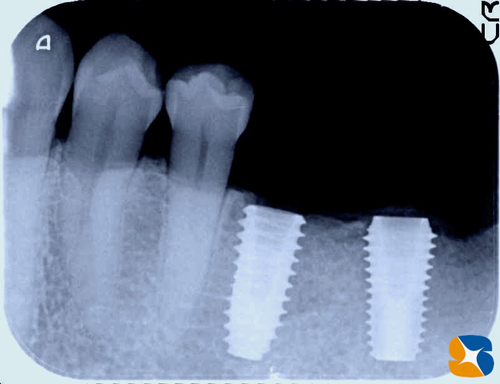

左下のレントゲン。

右上のレントゲン。